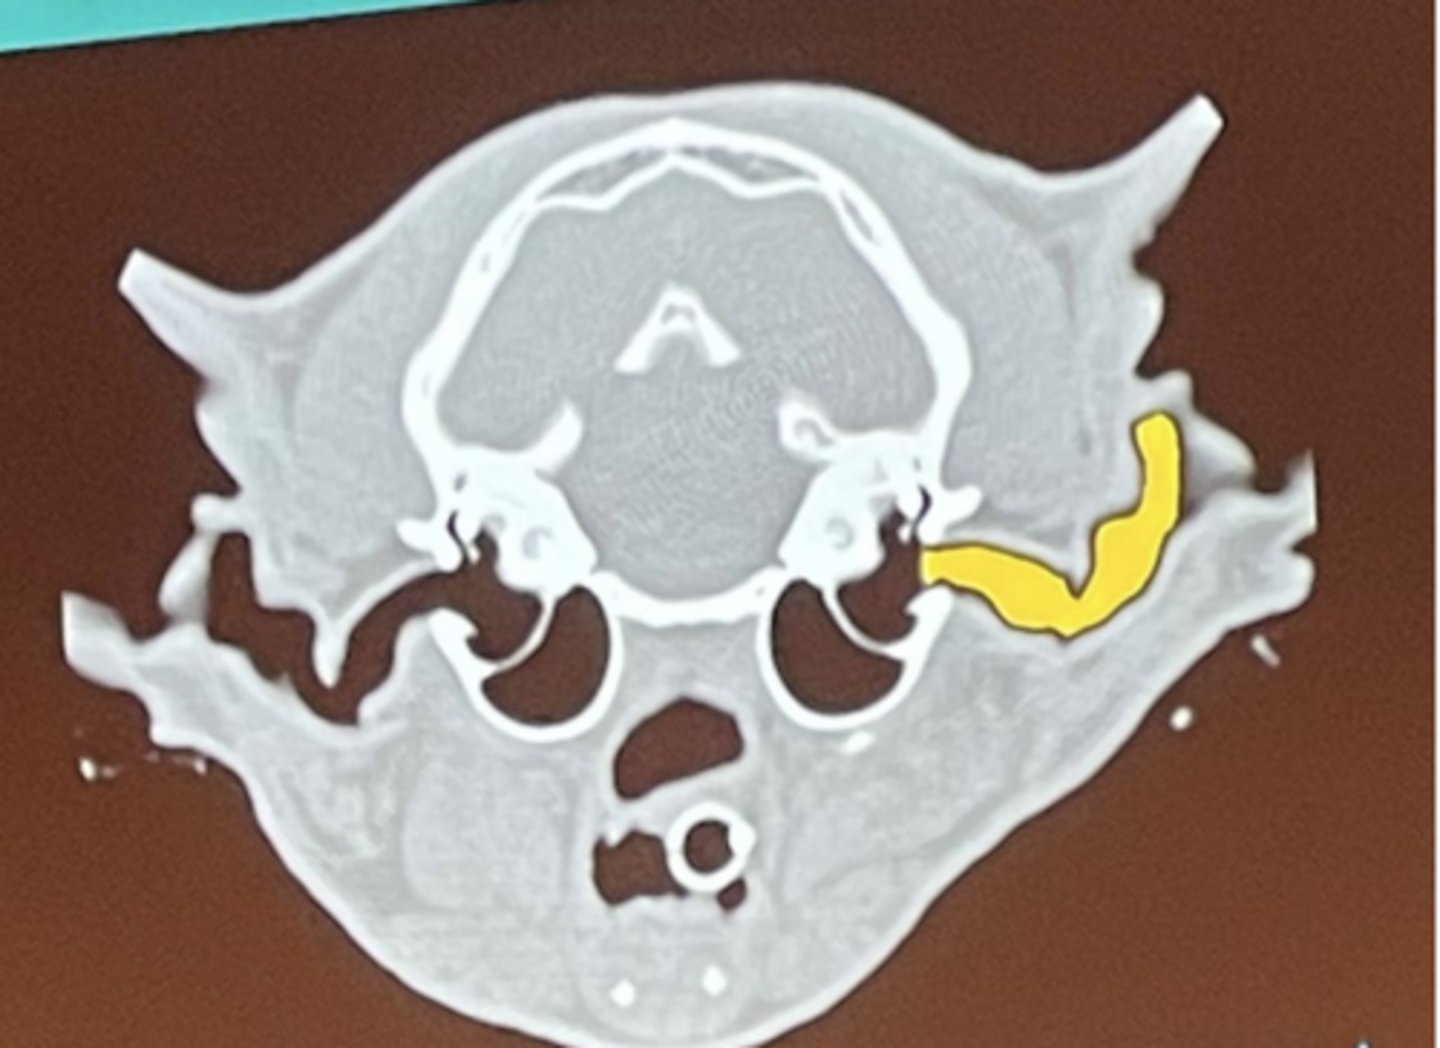

What is being highlighted in yellow?

external ear